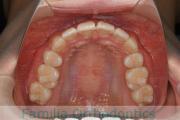

No.20V-499

- 主な症状:

- 上顎前突

- その他の症状:

- 叢生

- 年齢:

- 16歳

- 性別:

- 女性

- 抜歯部位

- 上:

- 44

- 下:

- 8558

- 主な使用装置:

- FEA

- 治療にかかった費用:

- 85万円

上の前歯が出っ歯気味なのを治したいということで来院されました。上下左右から小臼歯を抜歯して、歯科矯正用アンカースクリューを併用したマルチブラケット法により治療を行いました。動きの悪い歯やコントロールに苦労した場面があり、4年強・50回程度の通院が必要でした。

下顎前歯の叢生(でこぼこ、凹凸、ガタガタ)が著しく、後戻りのリスクが高い部位となります。